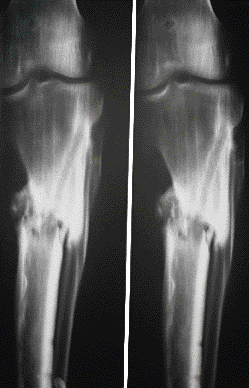

Si has dado con esta

web, probablemente es porque has sido diagnosticado de Osteomielitis.

Esta es una enfermedad que no te matará, pero es muy probable que

su tratamiento sea muy largo, e incluso puede que tengas que convivir

muchos años con ella.

Debes saber que la posible

curación de esta enfermedad pasa por un proceso largo y doloroso,

con cirugías muy agresivas. Es posible que la medicina no logre

vencer la infección y ésta se convierta en crónica.